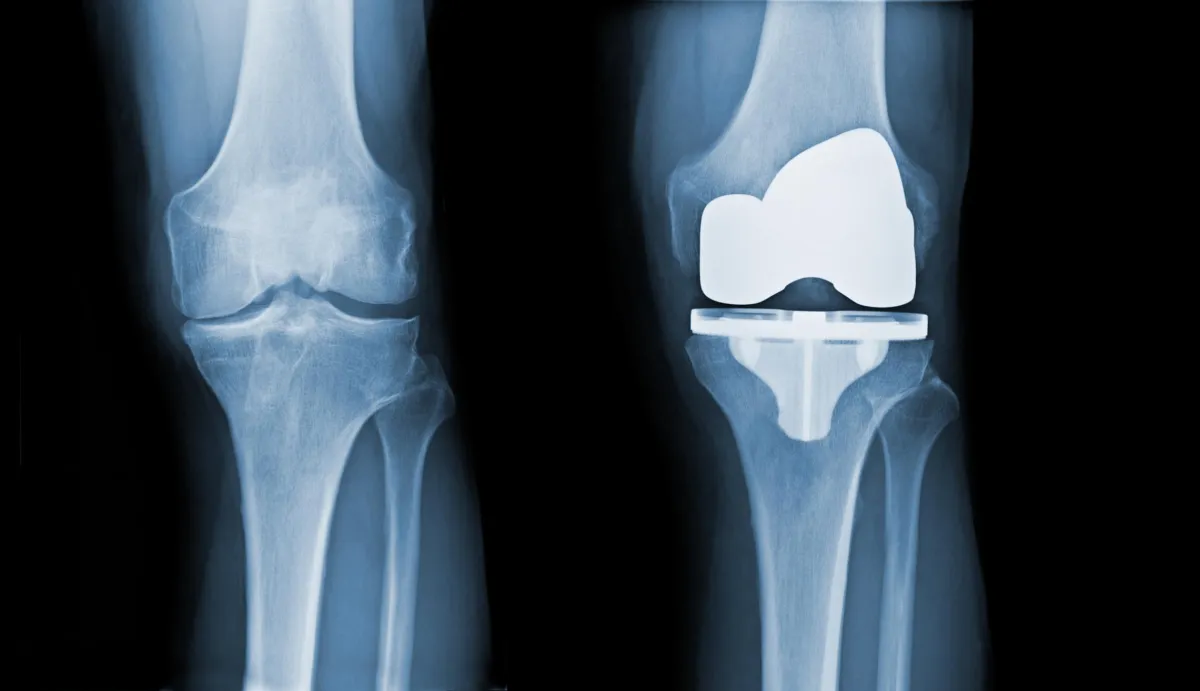

Osteoarthritis or Other Joint Problems: Some people call it “wear and tear” arthritis or degenerative joint disease. There are numerous risk factors including age, weight, prior injury and genetics.

Knee Stiffness or Loss of Motion: Common symptoms of arthritis include morning stiffness, swelling, reduced range of motion, pain when walking or getting up/down from a chair, pain with activity, cracking and popping of the knee.

Living with knee osteoarthritis can feel like driving on a worn-out tire – the protective cartilage in your joint thins, leading to painful friction and reduced natural lubrication.

Precision Matters: X-Ray Guided Injections

To ensure the gel reaches the precise area within your joint for maximum effectiveness, all our viscosupplementation injections are performed under X-ray guidance. This helps us deliver the relief you're looking for without any guesswork.